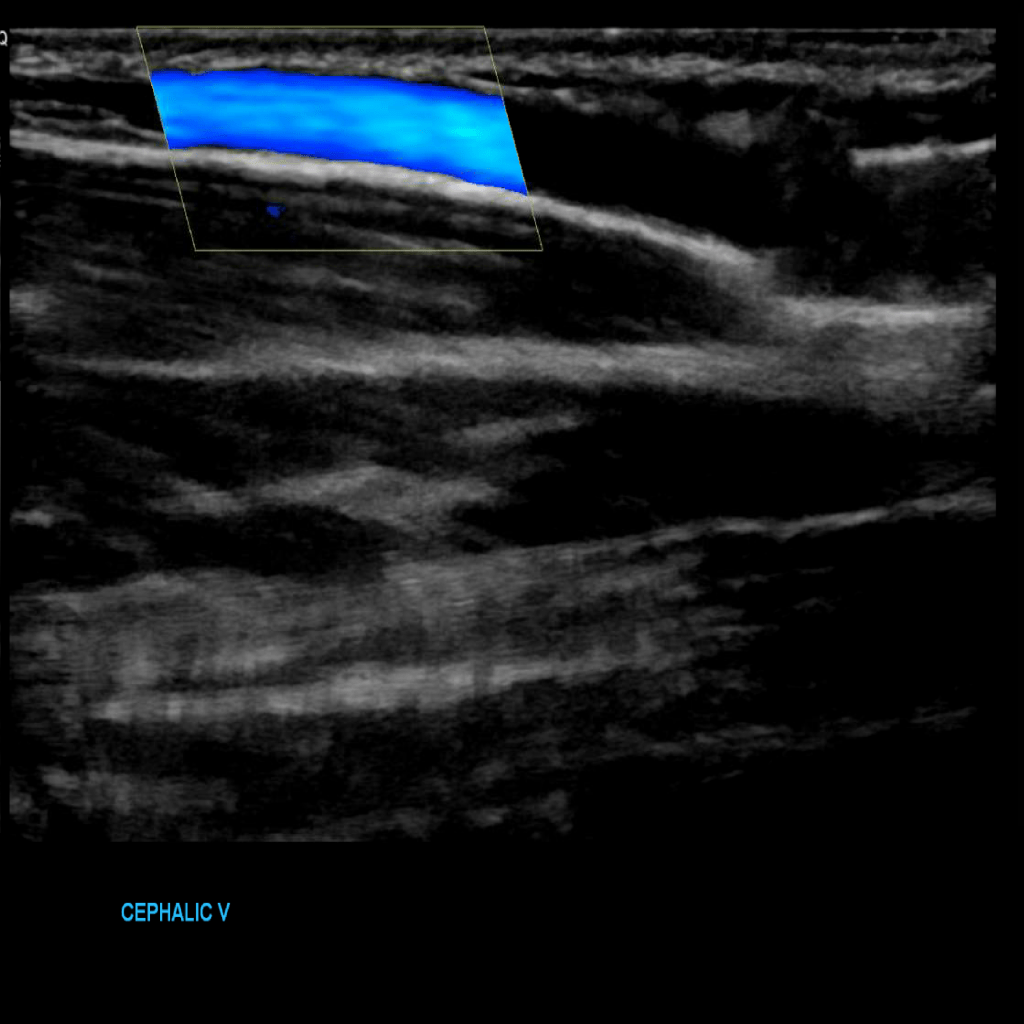

Scan the cephalic vein in grey scale, compression, color doppler and spectral doppler